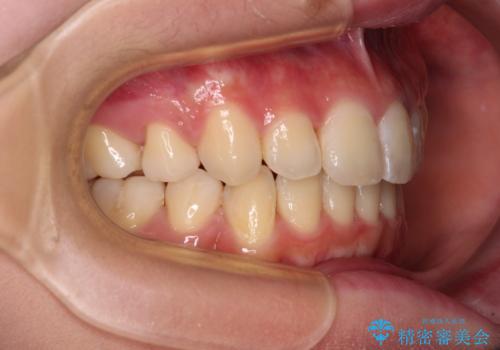

- 口元の閉じにくさを気にして来院された患者様です。

上下ともに歯列が前方に突出していたため、上下左右の第一小臼歯4本を抜去し、ワイヤー装置による矯正治療を行うこととしました。

舌の突出癖による影響もあったため、舌のトレーニングを並行して実施しました。